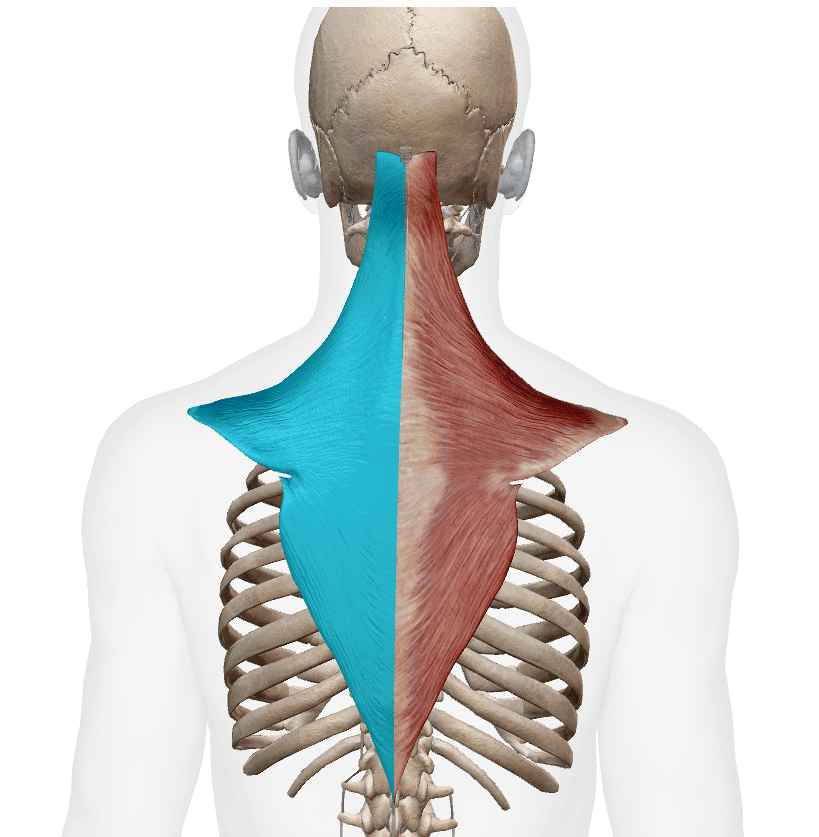

僧帽筋(そうぼうきん)は背部の一番表層部にある筋肉でそれぞれ上部僧帽筋、中部僧帽筋、下部僧帽筋に分類することができます。

僧帽筋は頚部および肩の後部上方を覆っている胸郭後方の平らな三角形筋です。

上部中部および下部繊維は、肩帯と頚部の動きを助けます。

上部僧帽筋、中部僧帽筋、下部僧帽筋の3つの部分が一緒に働くと肩甲骨は上方回旋と内転動作が同時に起こります。